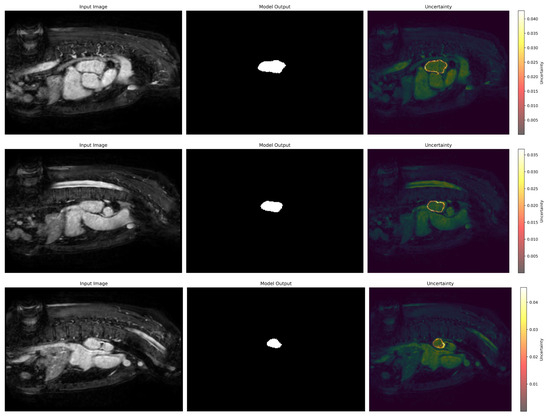

3.6. Uncertainty Estimation

We have also employed the Laplacian approximation method to estimate model uncertainty to enable a more robust prediction of our model which can help experts make decisions. Figure 11 highlights the areas where the model exhibits lower confidence along with ground truth and predicted regions. It can be seen that boundary regions exhibit lower confidence because these regions often pose challenges due to overlapping intensities or unclear anatomical delineation. Most of the segmented regions demonstrate low uncertainty, which reflects the model’s high confidence in its predictions for the majority of the structure. The integration of uncertainty estimation enhances interpretability by identifying regions that may require additional manual verification. This analysis underlines the robustness of the model and the value of uncertainty estimation in improving trust and decision-making in critical applications.

Figure 11.

Uncertainty estimation of the predicted results using Laplacian approximation.